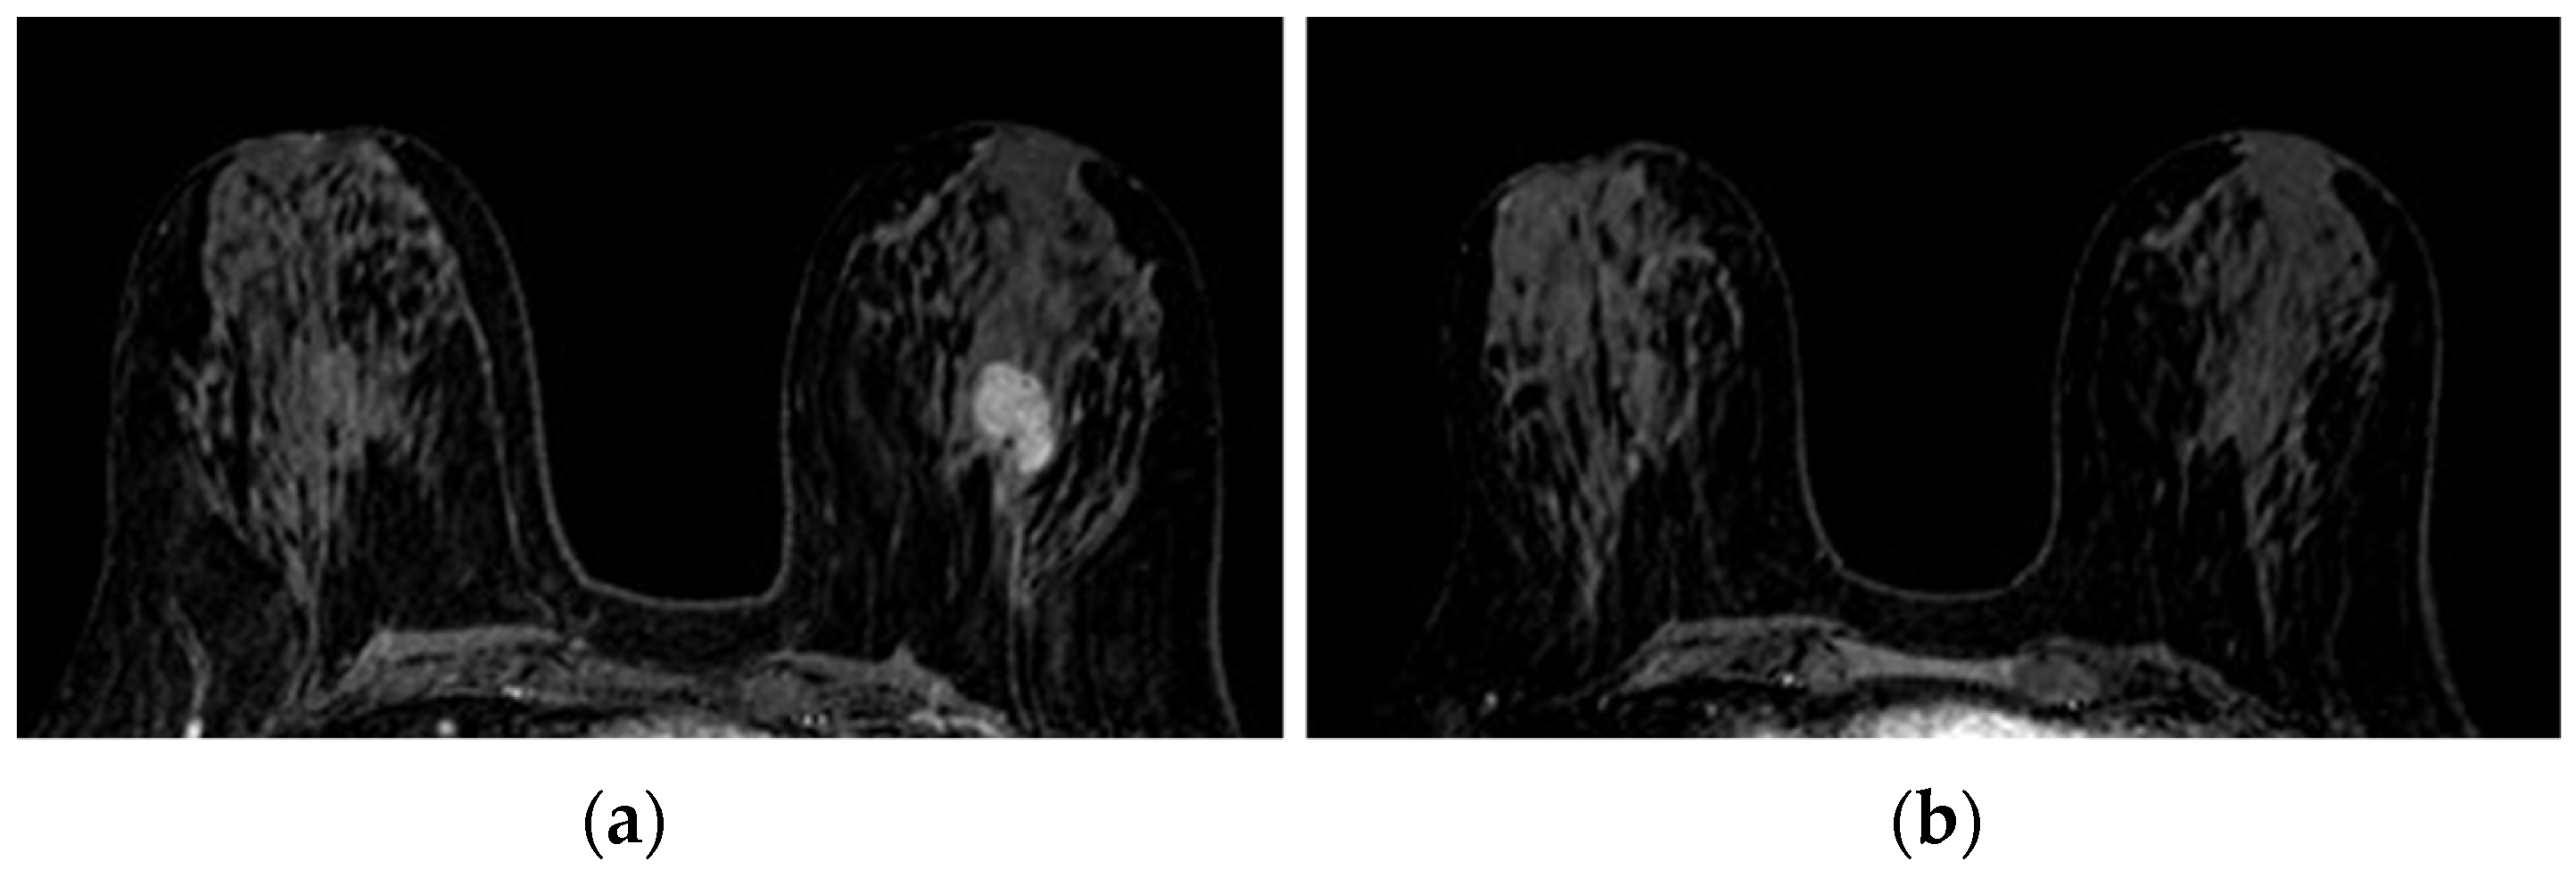

The operators’ assessments of FGT were carried out on the T2 morphological sequences and the first post-contrast acquisition of the dynamic sequence; otherwise, BPE evaluations were carried out on the first post-gadolinium dynamic sequence, as based on the literature [23,34]. FGT and BPE were classified according to ACR BIRADS [7] criteria in four groups: FGT in almost entirely fat (a), scattered fibro glandular tissue (b), heterogeneous fibro glandular tissue (c), extreme fibro glandular tissue (d), and BPE in minimal (I), mild (II), moderate (III), marked (IV), symmetric, or asymmetric. Examples of this classification are shown in Figure 1 and Figure 2.

Figure 2. Background parenchymal enhancement (BPE): (a) minimal; (b) mild; (c) moderate; (d) marked.

Figure 5. Complete pathological response (pCR): 2,5 cm deep retroareolar tumor on the left breast in the pre-treatment baseline survey ((a) triple negative) no longer visible at the end of the therapy cycles (b). Reduction of a BPE class (moderate to mild) is observed.